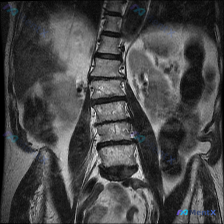

网上看到一份病例资料,用户标注提示是「脊柱侧弯」,但只给了一张腰椎MRI T2序列矢状位的图像和描述。 先把影像里的几个关键点列出来: - L4/5、L5/S1椎间盘信号明显减低(黑盘征),后缘突出,硬膜囊前缘受压 - 局部椎管矢状径变窄,黄韧带可能有肥厚 - 椎体序列生理曲度存在,未见明显楔形变或...

整理网上看到的一份影像讨论资料: 有人拿着一张腰椎T2加权矢状位MRI问是不是有脊柱侧弯。 先不直接说结论,先把这份影像的可见表现列出来,大家觉得第一时间应该关注什么? 影像可见表现(仅基于矢状位): 1. 腰椎多个节段(尤其是L3/L4、L4/L5、L5/S1)椎间盘T2信号减低,椎间隙高度有改变...

整理了一份腰椎影像资料,用户一开始问的是“这张图能看到脊柱侧弯吗?”。先说明一下,只有这份腰椎MRI T2加权矢状位序列。 先说说图里明确能看到的: 1. 多个腰椎椎间盘信号普遍减低,考虑广泛脱水退变; 2. L4/L5、L5/S1这些下腰段椎间盘后缘向椎管内突; 3. L3/L4、L4/L5、L5...